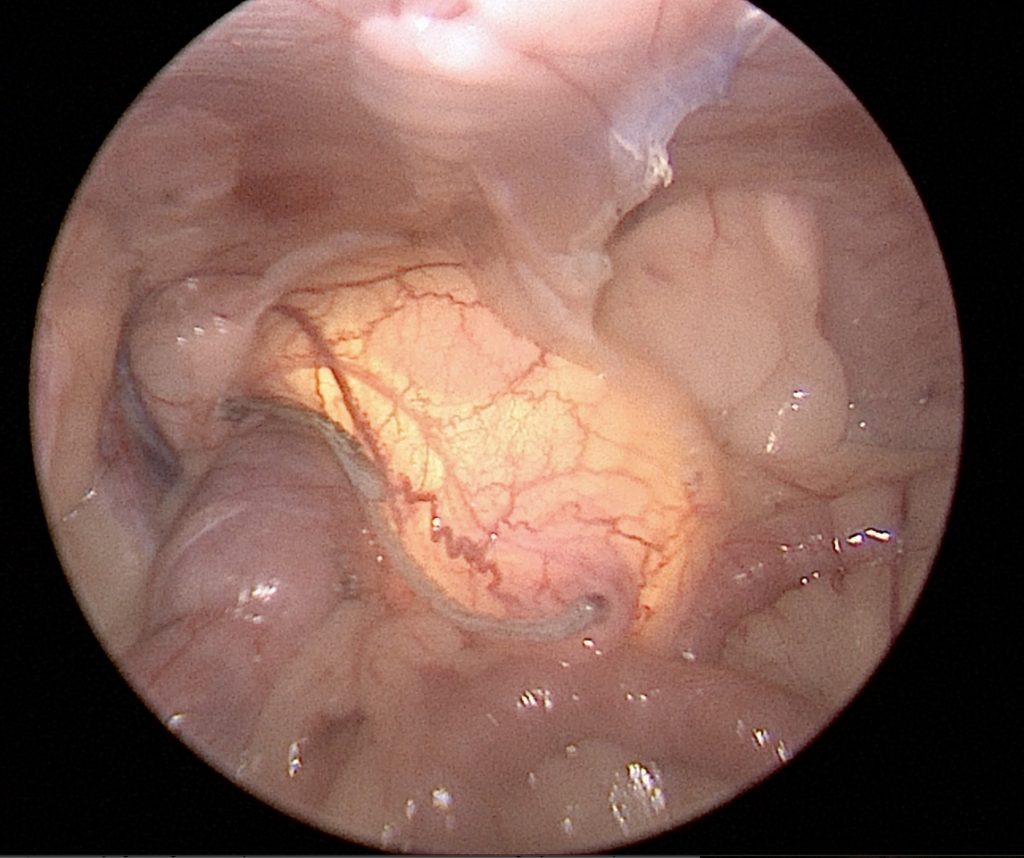

Laparoscopic partial cystectomy

Partial cystectomies are indicated for biopsy or resection of bladder tumors, bladder diverticulum, or patent urachus (Figures 8 and 9). With advanced imaging, such as CT, cystoscopy, and fluoroscopy, more specific information on the location of the bladder abnormality and its association with surrounding anatomy allows for better case selection for laparoscopic partial cystectomy.

Figure 8. Partial cystectomy with intra-operative cystoscopy guidance in a dog with transitional cell carcinoma. Photo courtesy Dr. Maureen Griffin-Waltz

Figure 9. Partial cystectomy has been performed for a urachal diverticulum and intracorporeal bladder closure is being performed with barbed suture. This patient also received a concurrent cystopexy for caudal pelvic bladder. Photo courtesy Dr. Eric Monnet

Resection of the bladder apex is feasible, with bladder closure via intracorporeal suturing alone or in combination with the use of a laparoscopic stapler or bipolar sealing device.26 Laparoscopy only allows visualization of the serosal surface of the bladder, limiting the ability to resect intraluminal tumors. However, the use of cystoscopy concurrently with laparoscopy can allow for a view of the bladder lumen for exact tumor resection and to prevent iatrogenic damage to surrounding structures such as the ureters.